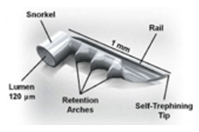

iStent®は開放隅角緑内障に対して眼圧を下降させる極低侵襲緑内障手術の際に使用されるMIGS(micro-invasive glaucoma surgery)デバイスです。単独での手術の際は自由診療となりますが、白内障手術と同時に行われる際には保険診療となります。

iStent®は、長さ横1mm縦0.12mmの非常に小さいデバイスです。緑内障手術は線維柱帯切除やEx-PRESS手術など各種の手術がありますが、今までの手術は目への侵襲が大きい手術でありました。

白内障手術の際に2.4mmの白内障手術創口からiStent®を線維柱帯にインプラントして、房水流出を妨げている線維柱帯に対して排出を改善し眼圧を下降させます。その為、侵襲の非常に少ない緑内障手術、極低侵襲緑内障手術として注目されております。臨床試験の結果では眼圧の下降と緑内障治療薬の低減が示されています。日本眼科学会HP[http://www.nichigan.or.jp/member/guideline/iStent.jsp]に詳細と論文がありますので、メリットデメリットなどご参考にして頂けますと幸いです。